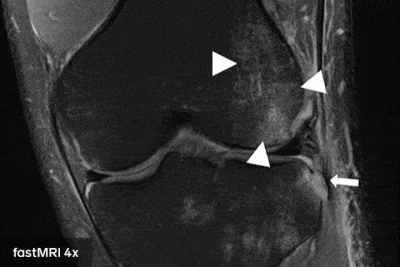

A través del estudio del equipo de investigación de inteligencia artificial de Facebook (FAIR) junto a radiólogos de NYU Langone Health se descubrió que es posible hacer resonancias magnéticas cuatro veces más rápido si se utiliza inteligencia artificial. Lo más importante es que las imágenes obtenidas conservan la calidad de las resonancias tradicionales.

El trabajo lleva el nombre de fastMRI y para llevarlo a cabo se entrenó a una máquina con muestras de resonancias de baja y alta resolución, utilizando esto para predecir cómo debería verse el resultado de una resonancia con solo un cuarto de la información que normalmente se procesa. Teniendo en cuenta que los resultados generales fueron buenos, esto puede representar un alivio tanto para pacientes como para médicos, ya que implica tener diagnósticos en menor tiempo.

La inteligencia artificial puede general los mismo resultados utilizando menos información porque ya aprendió la idea de como se ve un scan de una resonancia magnética analizando los datos que se le dieron en el entrenamiento. Usa todo su entrenamiento para predecir el resultado final.